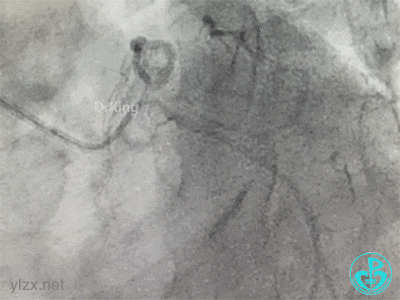

冠脉造影

右冠脉近中段不规则狭窄。短左主干中度狭窄,前降支开口严重狭窄,多功能造影导管推注造影剂时无反流,导管退出左主干开口造影发现左主干狭窄严重。

更换指引导管,导丝分别进入前降支和回旋支,球囊分别扩张前降支开口和回旋支开口,IVUS确认左主干及分支开口病变,前降支中段植入支架,对角支开口球囊扩张。

左主干分叉病变采取Crush双支架术式,回旋支开口植入支架,前降支开口球囊挤压后左主干到前降支植入支架(Crush双支架术式)。